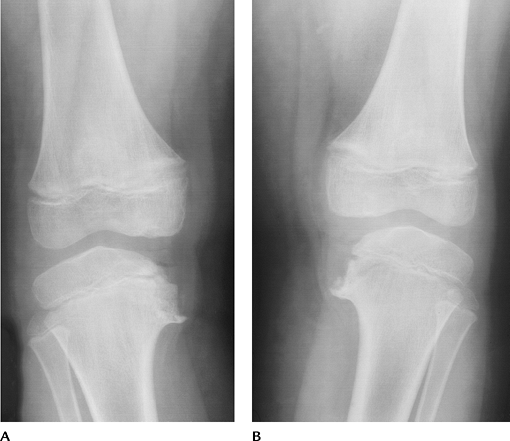

![]() |

FIGURE 5-64 Standing views of the knee showing medial compartment narrowing, more evident on the right, caused by osteoarthritis.